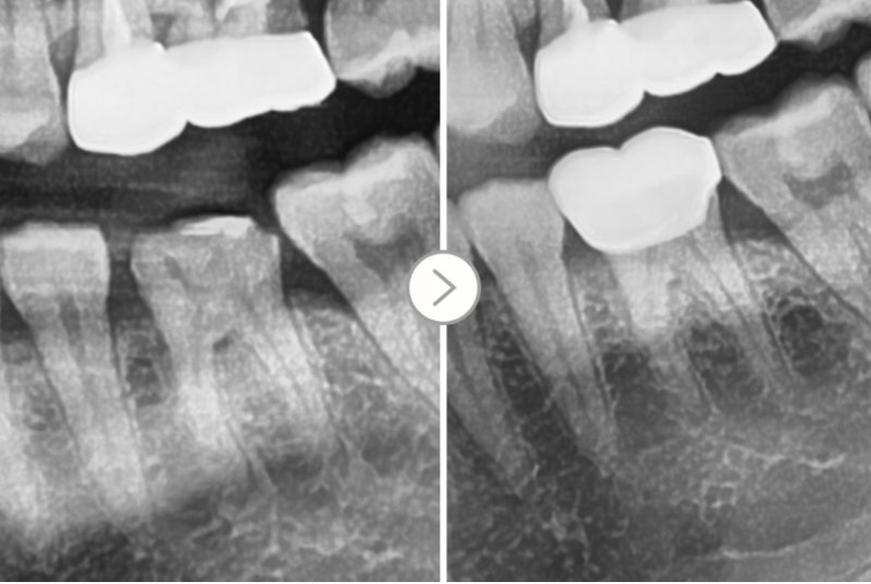

Trường hợp dưới đây là ảnh một bệnh nhân

đến bệnh viện vì mão răng rơi ra khi ăn thạch.

▲ Gắn lại mão răng bị rơi một cách đơn giản